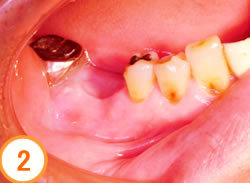

下顎の奥歯が1本ありません

レントゲンで欠損とその周囲の状態を調べます

埋入するインプラントを決定します

手術時間は30分程度でした

インプラントのX線像

セラミックの歯が入り良く噛めるようになりました